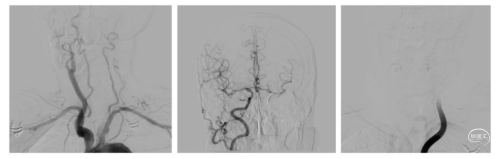

手术过程 造影见右侧颈总动脉造影未见后交通开放,未见基底动脉尖下图1。造影导管超选至右侧椎动脉造影,基底动脉中段闭塞,闭塞远端通过软膜代偿可显影,基底动脉尖显影不佳下图2、3。左侧锁骨下动脉造影见V1段、V2段严重迂曲,遂选择右侧优势椎入路。下图4、5

1、在路图下将260cm长导丝、造影导管超选至右侧椎动脉V2段。撤出造影导管,长导丝交换6F堑远端通路导管及088颅内血栓抽吸导管至V2末端。下图1

2、Transend 200mm 微导丝+Rebar 18 微导管同轴技术将6F远端通路导管及088颅内血栓抽吸导管导引至闭塞段。下图2

3.缓慢上推 088颅内血栓抽吸导管成功上至闭塞段。下图1

4.6F远端通路导管负压抽吸下撤出体外,再次使用088颅内血栓抽吸导管进行充分抽吸,取出部分血栓。下图2

造影显示:未见血管开通。

行球囊穿梭辅助088到达血栓位置:

▪微导丝通过闭塞段,在闭塞远端摆动良好,判断闭塞段相对较短。

▪输送2.0×12mm颅内球囊扩张导管至闭塞段,同时轻柔推送088颅内血栓抽吸导管,顺利通过分叉部,接近闭塞段。088颅内血栓抽吸导管到达目标位置后,充分扩张球囊,缓慢完成球囊穿梭。下图1、2

撤出颅内球囊扩张导管,顺利推送088颅内血栓抽吸导管至基底动脉尖持续抽吸1分钟,保持负压抽吸回撤。下图1

回撤后见血流通畅,基底动脉尖完全再通,无明显血栓逃逸。下图2

观察15分钟以后复查造影,血流维持良好,无明显回缩,(下图3)结束手术。抽吸取出的血栓,下图4